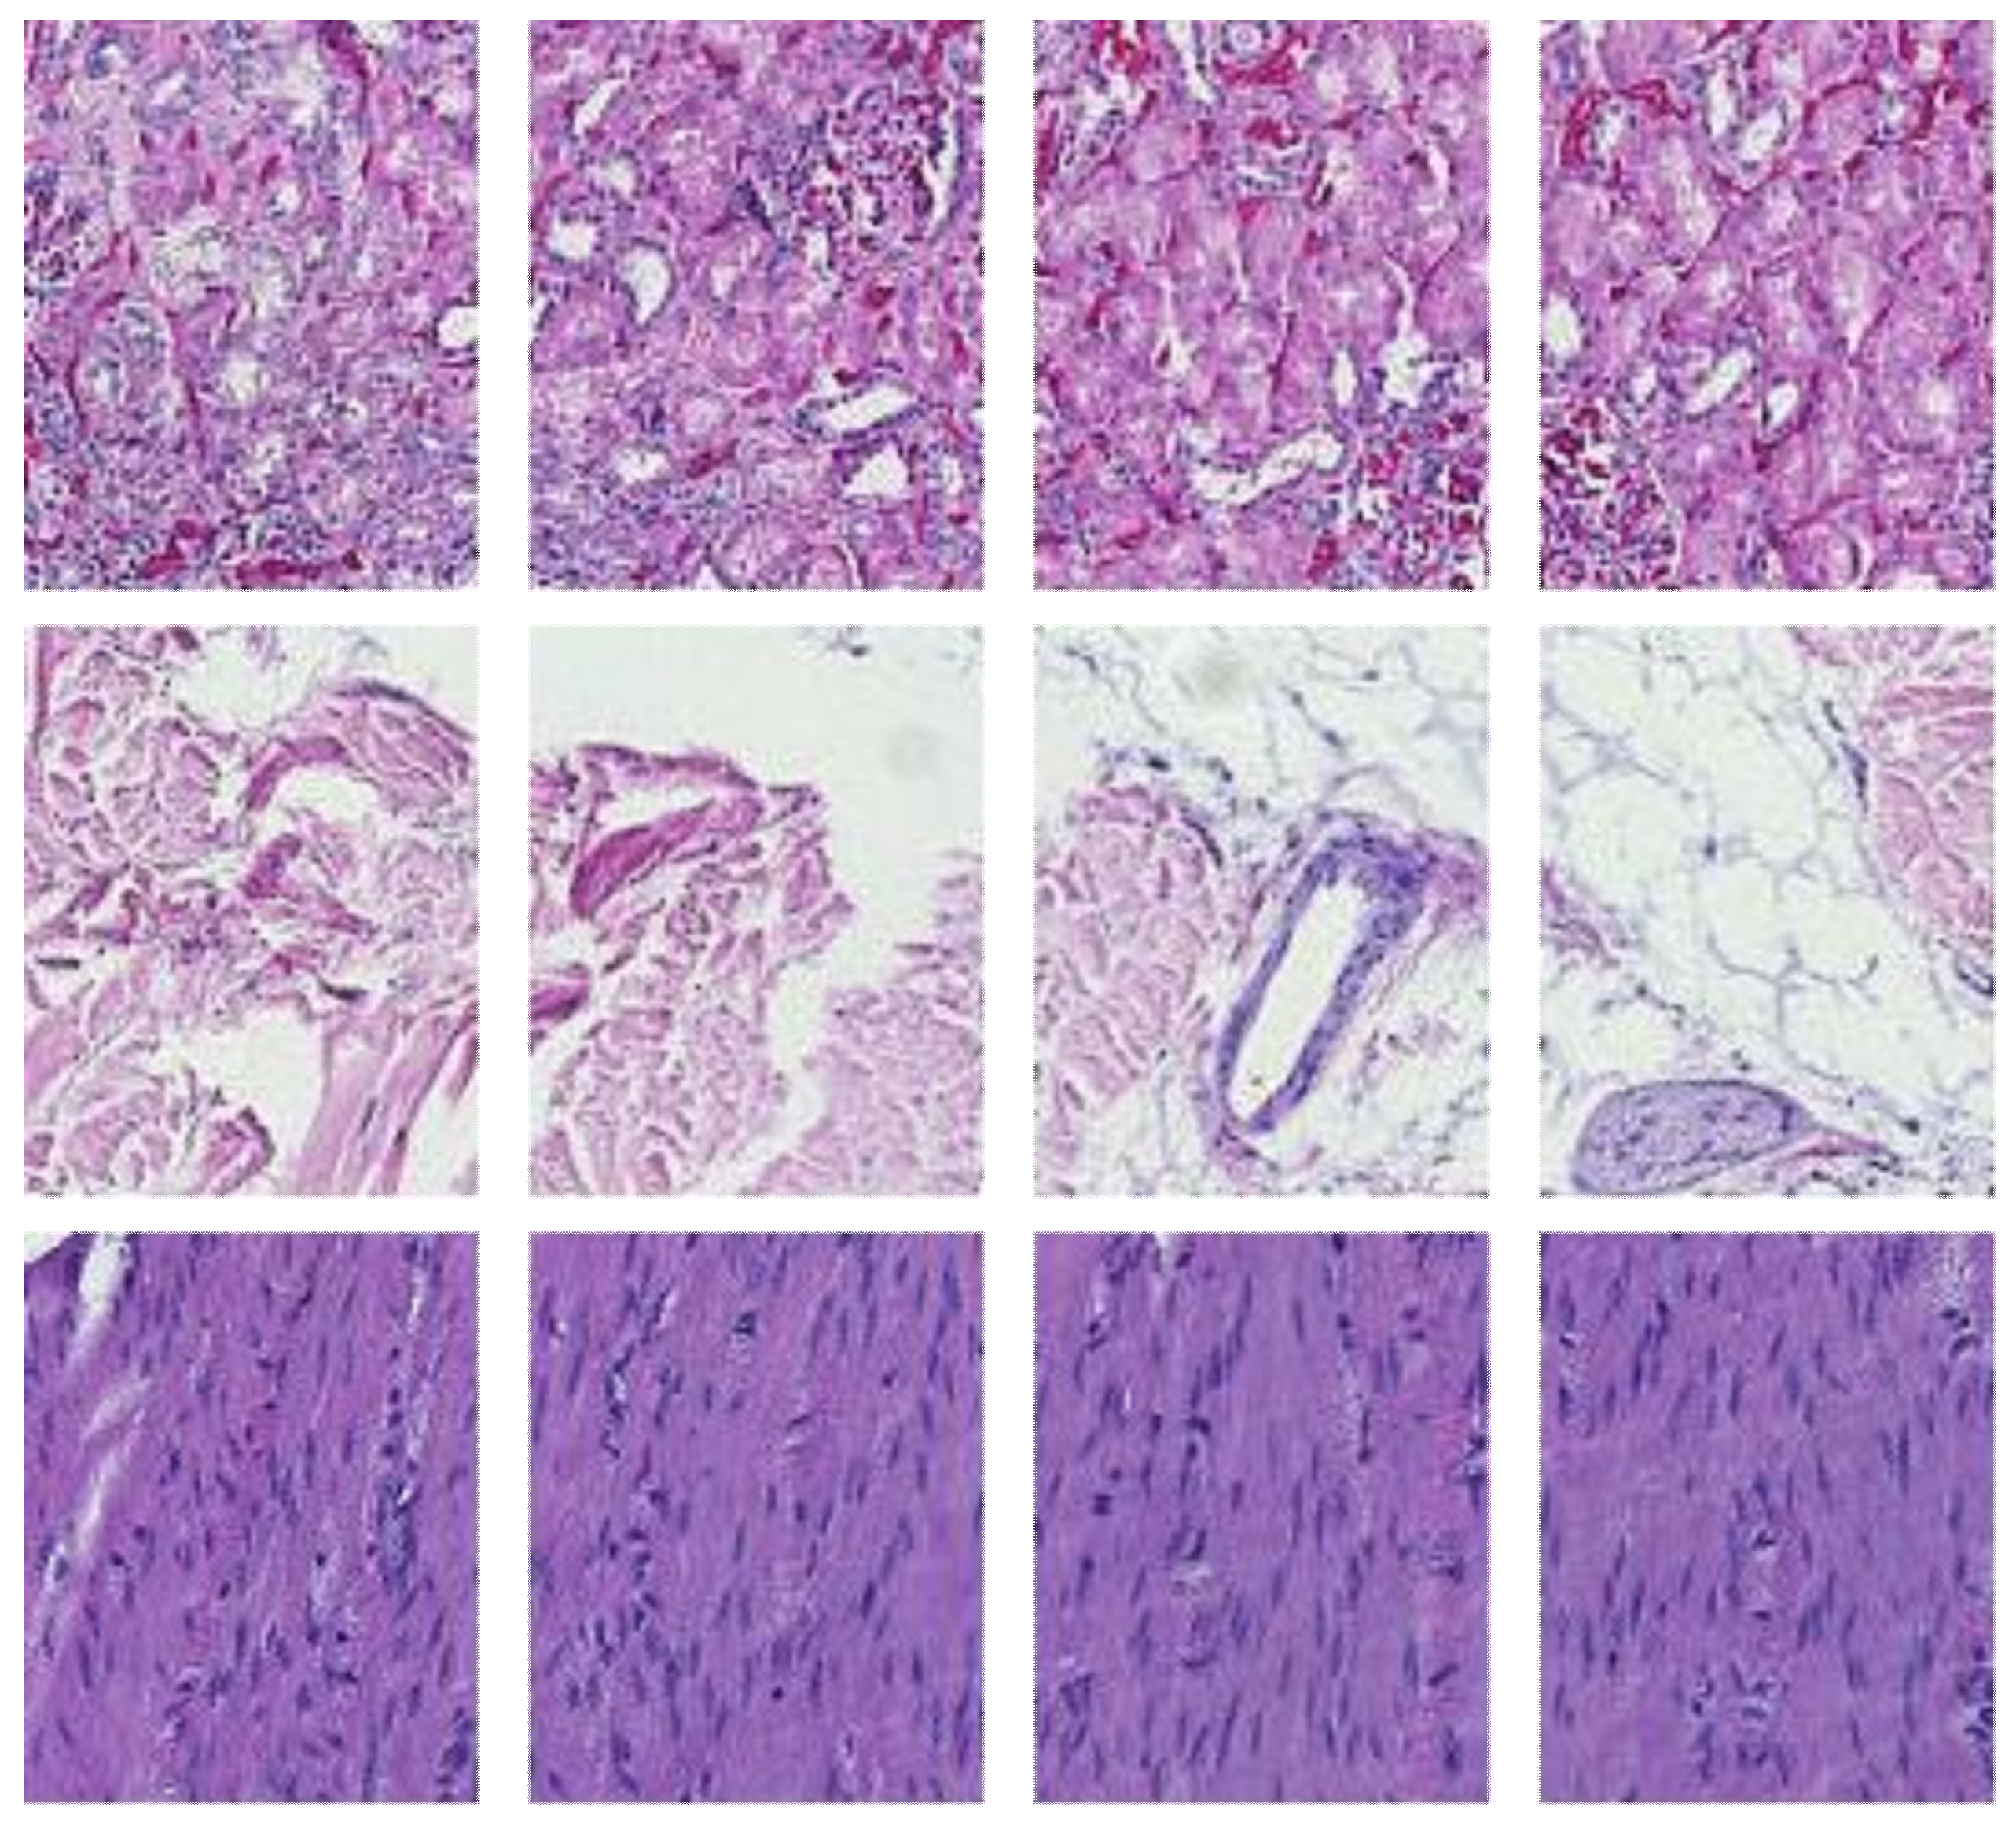

In the data collection phase, we obtained H&E-stained slides used in an external quality assessment (EQA) round organized by Labquality (Helsinki, Finland), a company providing external quality assessment schemes for clinical laboratories. The slides had a tissue microarray section consisting of three 6 mm punch biopsies. The punches were taken from normal human kidney, skin, and colon samples. The samples were anonymous formalin-fixed and paraffin-embedded routine histologic samples from a reference pathology laboratory. The EQA round was organized such that unstained 3 µm sections were sent to laboratories participating in the EQA scheme. The laboratories were asked to stain the slides by the H&E method they use in their daily practice. Altogether 66 laboratories from 11 countries returned the slides for the assessment. After that, the slides were digitalized with a NanoZoomer-XR (Hamamatsu Photonics) slide scanner with a 20× objective (scanning resolution 0.46 μm/pix); Figure 1 shows a random example of a stained slide.

Figure 1.

Randomly chosen WSI, label 1 for kidney, 2 for skin, and 3 for colon tissue.

The raw whole slide image (WSI) size was 44,214 by 44,214 pixels; the analysis was coordinated between the Central Finland Biobank, Nova Central Finland Hospital, and the Digital Health Intelligence Laboratory and Spectral Imaging Laboratory of the University of Jyväskylä, Finland. As part of the experiential pipeline, the WSIs were further processed as detailed in the proceeding sections.